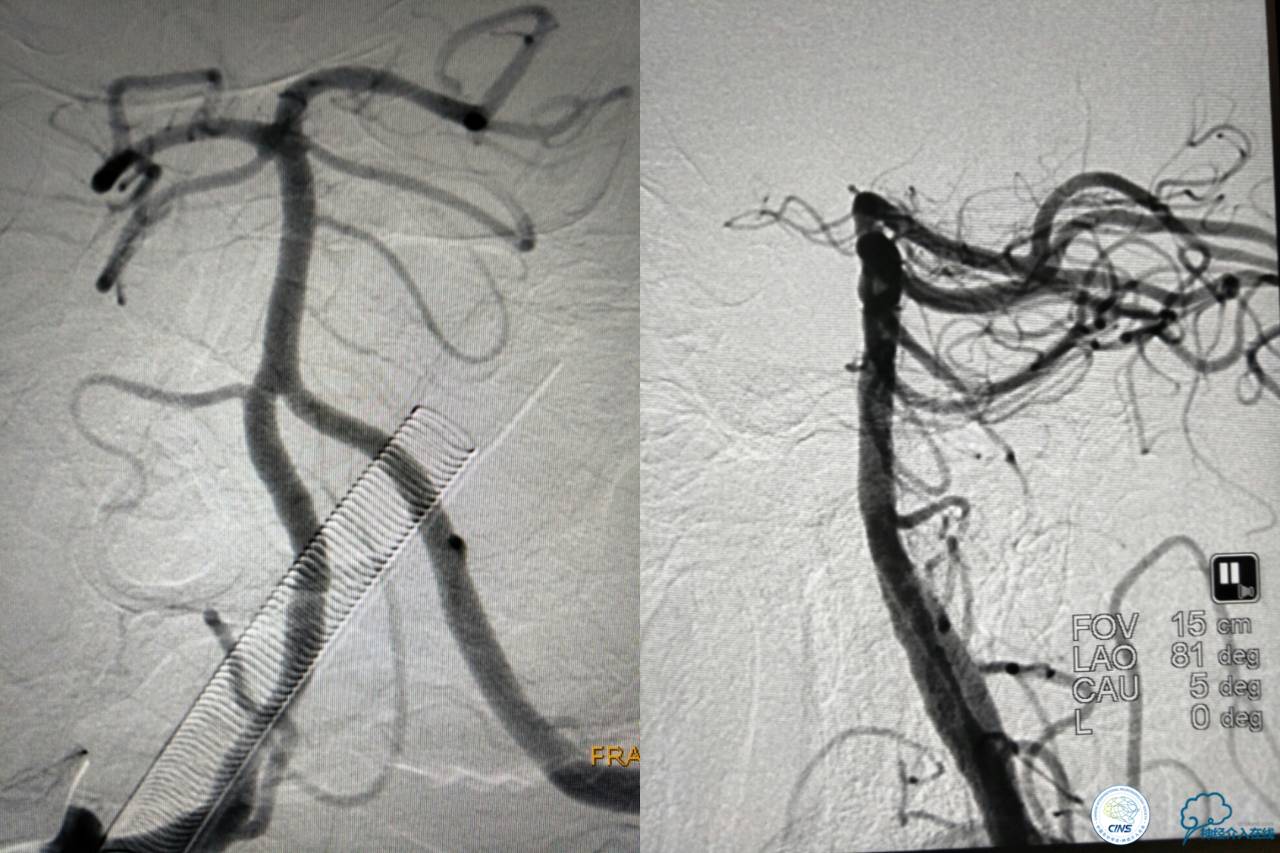

没错,没看错!血管成功实现再通,术中取栓的栓子如下。

术后

术后生命体征平稳,成功撤呼吸机,肌力较前好转,复查头颅CT:

右侧丘脑高密度影,右侧枕叶可能也有梗死,祈祷慢慢恢复吧!